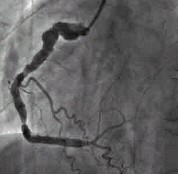

例2,男,40岁,以阵发性胸闷三年,加重一月入院。查体:心界扩大,心率74次/分,心尖区可闻及Ⅲ级收缩期杂音。心电图:V1~V4导联呈QS型,ST段抬高。冠状动脉造影示:LCX、RCA弥漫扩张,前向血流TIMIⅢ级;LAD开口100%闭塞。(图3,图4)。IVUS示:LCX、RCA显著扩张,未见明显动脉粥样硬化斑块。心脏彩超示:左心室前壁节段性运动减弱,心尖段室壁瘤形成;左心房内径39mm,左心室舒张末期前后径70mm;二尖瓣轻度关闭不全,三尖瓣轻度关闭不全;EF:41%。行冠状动脉搭桥手术(CABG)及室壁瘤切除术,术后随访4个月,无胸闷症状发生。

图3:例2冠状动脉造影显示前降支开口100%闭塞,回旋支显著扩张